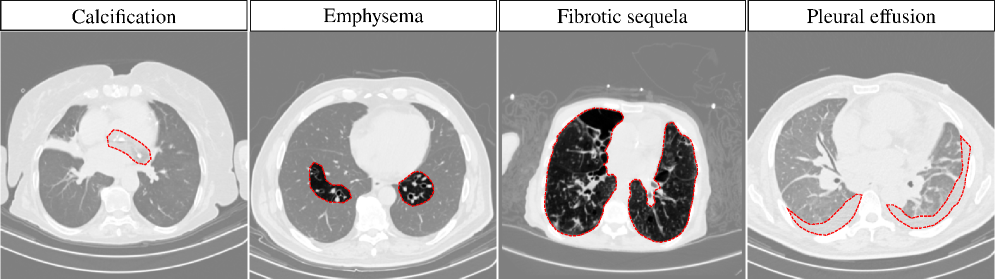

Refer to caption

Figure 1: Axial slices from 3D CT Scans, with abnormalities manually contoured in red, illustrating distinct visual characteristics.

Despite its clinical relevance, multi-label abnormality classification in 3D chest CT remains a highly challenging task due to the broad diversity of abnormalities, as illustrated in Figure 1. Furthermore, the volumetric nature of CT data necessitates the development of computationally efficient architectures that are scalable and suitable for real-world clinical deployment [2].